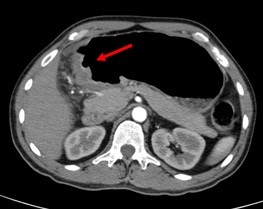

Computed Tomography Scan (CT Scan)

An X-ray that produces detailed cross-sectional images of your body, the Computed Tomography Scan (CT scan) takes many pictures as it rotates around you. These pictures are then combined into images of slices of the part of your body being studied by a computer.

The stomach can be viewed fairly through the CT scan and can often confirm the location of the cancer. The CT scan can also show organs near the stomach such as the liver, lymph nodes, and distant organs where the cancer might have spread. The CT scan can help determine the extent or stage of cancer and indicate whether surgery may be a good treatment option.